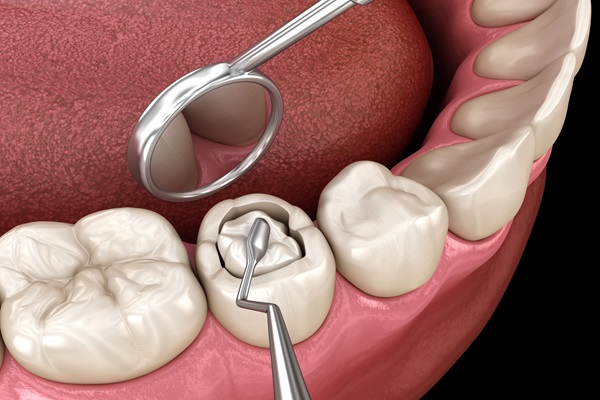

Oral lesion treatments target sores, ulcers, or abnormalities in the mouth, promoting early diagnosis and effective management for optimal oral health. Our advanced care helps prevent infections, ensures patient comfort, and supports overall well-being. This approach is essential for maintaining a healthy and pain-free mouth.